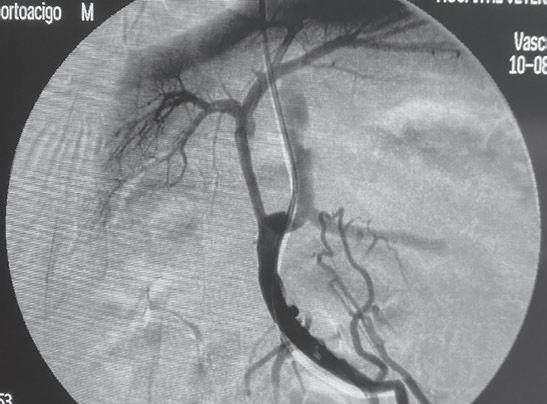

La radiología intervencionista es una especialidad que se encarga del diagnóstico y tratamiento de una gran cantidad de patologías de una forma mínimamente invasiva. Para realizar estos procedimientos es imprescindible disponer del equipamiento adecuado, tener nociones tanto de la instrumentalización como de las diferentes técnicas, y conocer con precisión la anatomía del paciente. Se trata de técnicas cada vez más implementadas en la clínica diaria ya que permiten solucionar diferentes patologías con una menor agresión a nivel tisular, una rápida recuperación, son procedimientos sin dolor, rápidos y seguros, suponen un menor coste respecto a otras cirugías invasivas, y constituyen una alternativa terapéutica a pacientes que no se pueden operar de forma convencional. Entre las más frecuentes destaca el cierre del conducto arterioso persistente, valvuloplastias en estenosis pulmonar, oclusión de shunts portosistémicos, implantación de marcapasos y colocación de stents

En 1953, el Dr. Sven Seldinger describió la colocación percutánea de catéteres vasculares mediante acceso con aguja, técnica que posteriormente se denominó método Seldinger, y que sentó las bases del desarrollo de la radiología intervencionista. En 2005, el Dr. Chick Weisse creó el primer servicio veterinario de radiología intervencionista en la Facultad de Veterinaria de la Universidad de Pensilvania. Desde entonces, esta especialidad ha logrado grandes avances permitiendo el desarrollo de nuevas técnicas y dispositivos, así como un número cada vez mayor de indicaciones para estas técnicas quirúrgicas.

La radiología intervencionista, también conocida como radiología vascular e intervencionista, es una especialidad que se encarga del diagnóstico y tratamiento de una gran cantidad de enfermedades de una manera mínimamente invasiva. Se realiza mediante un abordaje guiado por distintas técnicas de imagen como, por ejemplo, la ecografía, la fluoroscopia o la tomografía computarizada, para alcanzar la zona a diagnosticar o tratar.

imágenes basadas en rayos X y posteriormente las convierte en una señal de vídeo en tiempo real. Estas imágenes pueden manipularse ofreciendo funciones como la angiografía de sustracción digital, mapeo vascular y ampliación. Respecto a una radiografía, la exposición de rayos X necesaria para realizar una fluoroscopia es baja, pero debido a la duración de las series de imágenes que habitualmente se toman, el nivel de exposición en los pacientes suele ser elevado. Por lo tanto, es importante controlar el tiempo de exposición y llevar un registro de este. El fluoroscopio debe estar situado en una sala adecuada para su uso seguro, y todo el personal que entre en la sala de fluoroscopia debe protegerse de la radiación utilizando un delantal plomado, protectores de tiroides y gafas plomadas.